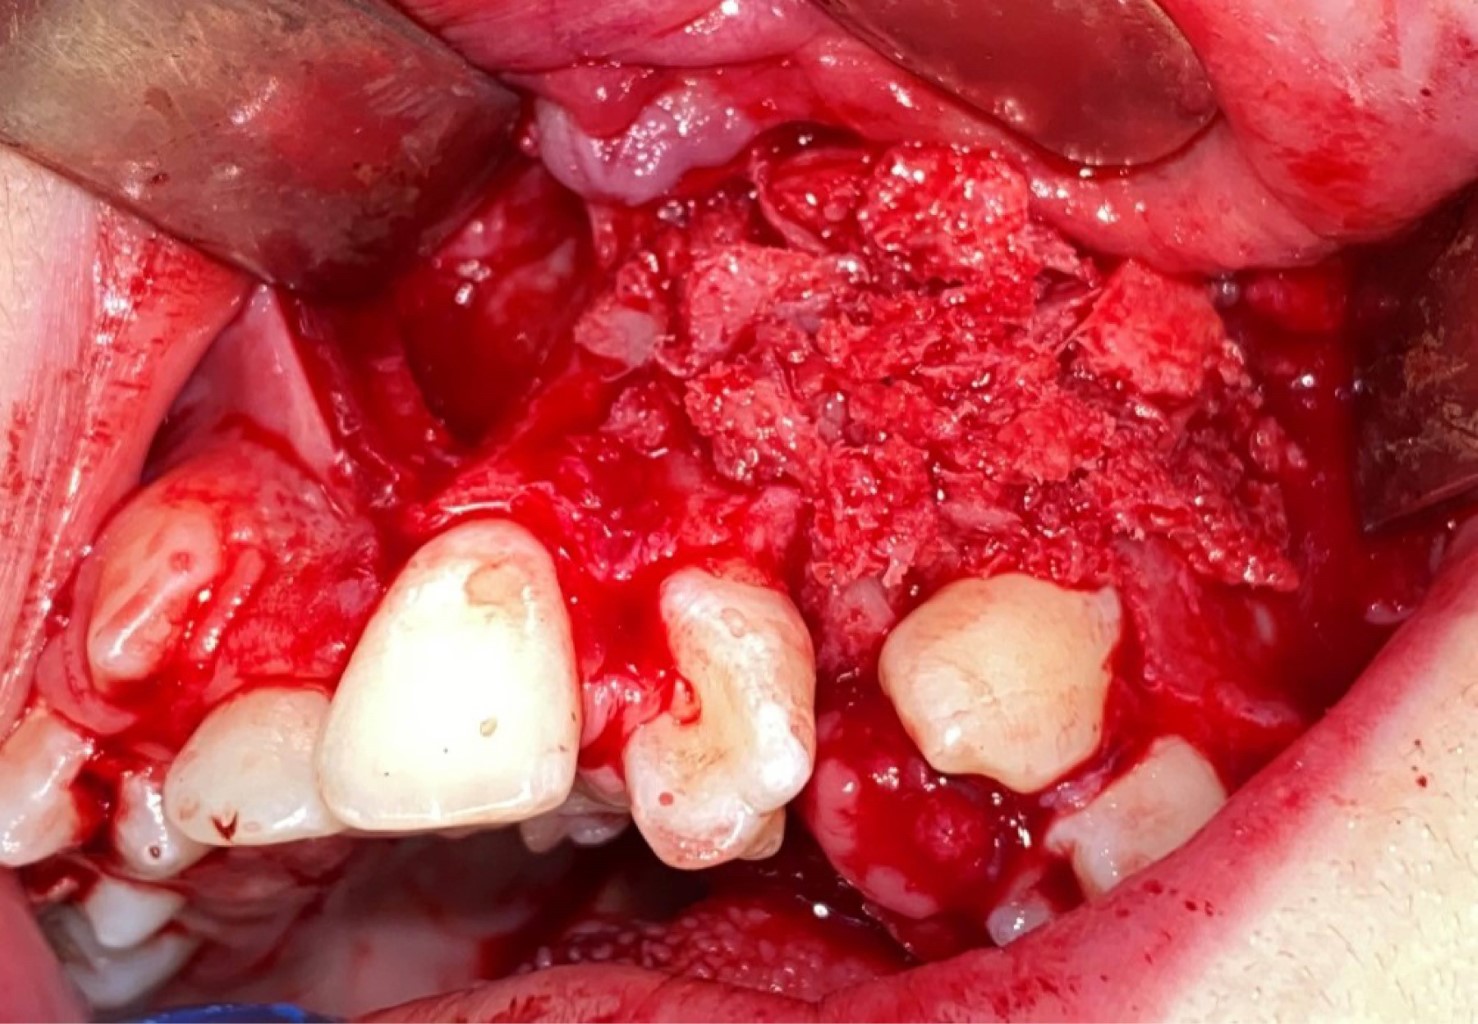

Use of plasma rich in growth factors with anterior iliac crest graft for repair of nasoalveolar cleft in patient with unilateral cleft lip and palate

Gómez-Hernández KA, Alonso-Moctezuma A, Castilla-Canseco H, Cuen-Lara E

Introduction: nasoalveolar fissures are common in patients with cleft lip and palate. Surgical treatment continues to feel the autologous bone graft with anterior iliac crest, however, the main complication of the surgical site is bone exposure and graft loss. Objective: the objective of this clinical case is to show how the use of biomaterials such as plasma rich in growth factors allows to improve the integration of the bone graft by avoiding the dehiscence of the gum. Case presentation: we present a 36-year-old female patient with cleft lip palate and nasoalveolar fissure treated by bone graft of nasoalveolar fissure and plasma rich in growth factors, presents adequate integration of the graft and scarring of soft tissue at six and 12 months postoperatively. Conclusions: the use of biomaterials such as plasma rich in growth factors is suggested to avoid dehiscence and graft compromise, thus avoiding a second surgery.

Figure 2